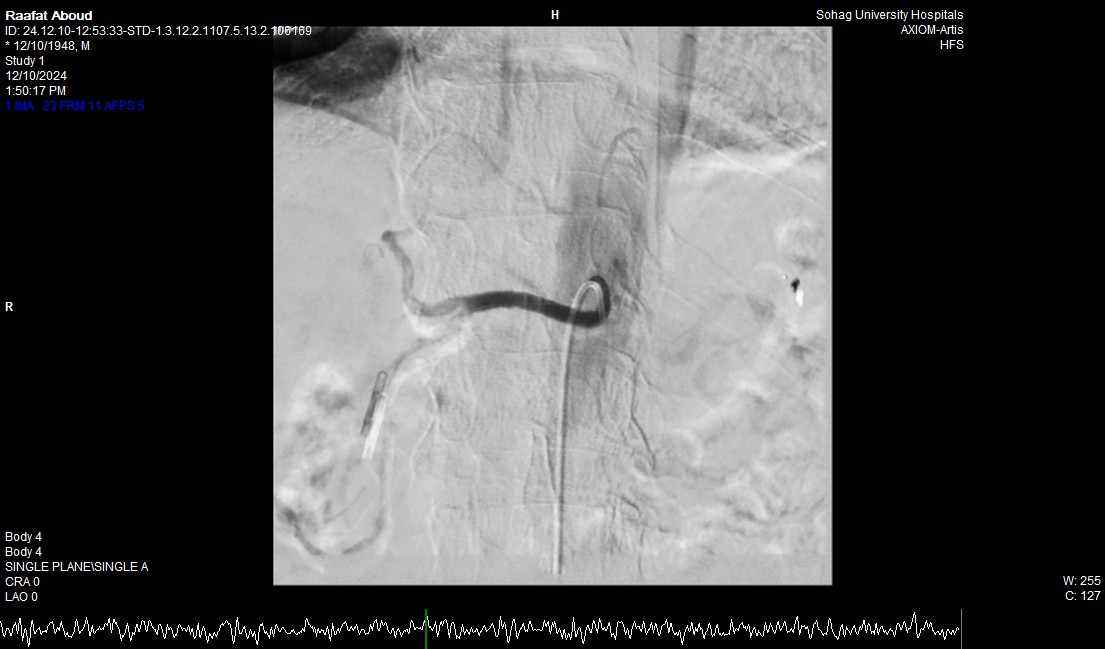

جامعة سوهاج.. وفي خطوة لاحقة، تم استدعاء فريق الأشعة التداخلية الذي تمكن من إغلاق الشريان النازف بشكل عاجل باستخدام جهاز القسطرة، ما ساهم في استقرار حالة المريض.

جامعة سوهاج.. أشار الدكتور نايل عبد الحميد، رئيس قسم أمراض الباطنة، إلى أن التدخل الطارئ باستخدام المنظار والقسطرة الشريانية جنب المريض اللجوء إلى الجراحة، خاصة مع عمره المتقدم. وأضاف أن حالة المريض أصبحت مستقرة، مع توقف النزيف وتحسن في وظائف الكلى والكبد، وتم نقله من وحدة الرعاية المتوسطة إلى القسم الداخلي للمتابعة.

جامعة سوهاج.. أكد الدكتور محمد زاكي، رئيس قسم الأشعة، أن مثل هذه الحالات تعد من أخطر الطوارئ الطبية، حيث يتطلب التعامل معها إجراء قسطرة شريانية عاجلة لإيقاف النزيف. وأضاف أن وحدة الأشعة التداخلية مزودة بجهاز أشعة محوري متقدم مخصص لمثل هذه التدخلات، مشيرًا إلى أن هذا النجاح يعكس التعاون المثمر بين أقسام المستشفى المختلفة ووحدة الأشعة التداخلية لتقديم خدمات متميزة للمرضى.